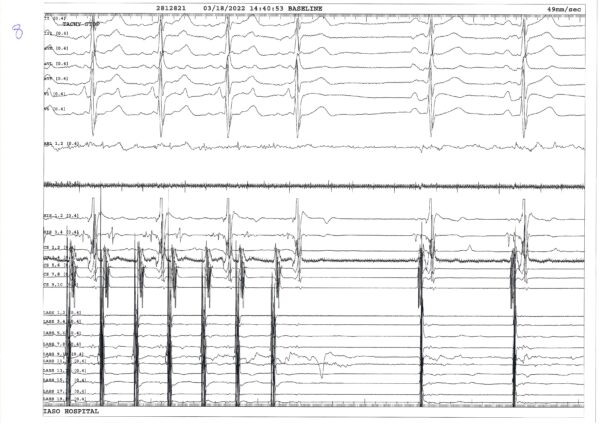

Με διαδοχική μετακίνηση των καθετήρων, αρχικά, κατασκευάστηκε το τρισδιάστατο μοντέλο του αριστερού κόλπου και των ΠΦ (Εικόνες, CD). Από τον έλεγχο που έγινε εντός του άντρου των ΠΦ διαπιστώθηκε επανασύνδεση στις δεξιές ΠΦ και έγινε απομόνωση της δεξιάς άνω ΠΦ με σημειακή εφαρμογή ενέργειας στην περιοχή μεταξύ των δεξιών ΠΦ (Καταγραφή 3). Επί της κολπικής ταχυκαρδίας (ΑΤ 1) έγινε χάρτης διέγερσης. Διαπιστώθηκε ότι επρόκειτο για κύκλωμα περί την οροφή με ανιούσα φορά στο οπίσθιο τοίχωμα και διέλευση του ερεθίσματος από κενό στην δεξιά πλευρά της προηγούμενης γραμμικής βλάβης οροφής (Video 1). H δοκιμασία παράσυρσης που έγινε από το οπίσθιο τοίχωμα ήταν θετική (Καταγραφή 3). Για την κατάλυση της κολπικής ταχυκαρδίας (ΑΤ 1) χορηγήθηκε ενέργεια στο κενό της γραμμής οροφής, όπου είχαμε αργή διέλευση του ερεθίσματος, με αποτέλεσμα την άμεση μετάπτωση της ταχυκαρδίας σε άλλη μορφή με άπω προς εγγύς αλληλουχία στο στεφανιαίο κόλπο και μήκος κύκλου 330 ms (ΑΤ 2) (Καταγραφές 5,6). Επίσης διαπιστώθηκε μικρής έκτασης επανασύνδεση στην δεξιά κάτω ΠΦ που συμπληρώθηκε (Καταγραφή 6). Με την μετακίνηση των καθετήρων έγινε νέος χάρτης διέγερσης για την ΑΤ 2 που έδειξε κύκλωμα μικροεπανεισόδου στην ακρολοφία μεταξύ των αριστερών ΠΦ και του ωτίου (Video 2A– 2B). Στην περιοχή αυτή καταγράφονταν κατακερματισμένο κολπικό ηλεκτρόγραμμα το οποίο σε χρονική διάρκεια κάλυπτε >30% του μήκους κύκλου (Καταγραφή 7). Η κατάλυση στην περιοχή αυτή τερμάτισε άμεσα την ταχυκαρδία (Καταγραφή 8) και συνεχίστηκε μέχρι την απομείωση των δυναμικών.

Ακολούθως, έγινε απομόνωση του οπίσθιου τοιχώματος αρχικά με γραμμή στο έδαφος του αριστερού κόλπου. Με την ολοκλήρωση της γραμμής εδάφους άλλαξε η αλληλουχία στον κυκλοτερή καθετήρα που ήταν τοποθετημένος στο οπίσθιο τοίχωμα (Καταγραφή 9). Η ολοκλήρωση της απομόνωσης του οπίσθιου τοιχώματος έγινε με συμπλήρωση του κενού στην γραμμή οροφής, οπότε και είχαμε πλήρη εξάλειψη των δυναμικών από το οπίσθιο τοίχωμα (Καταγραφή 10).